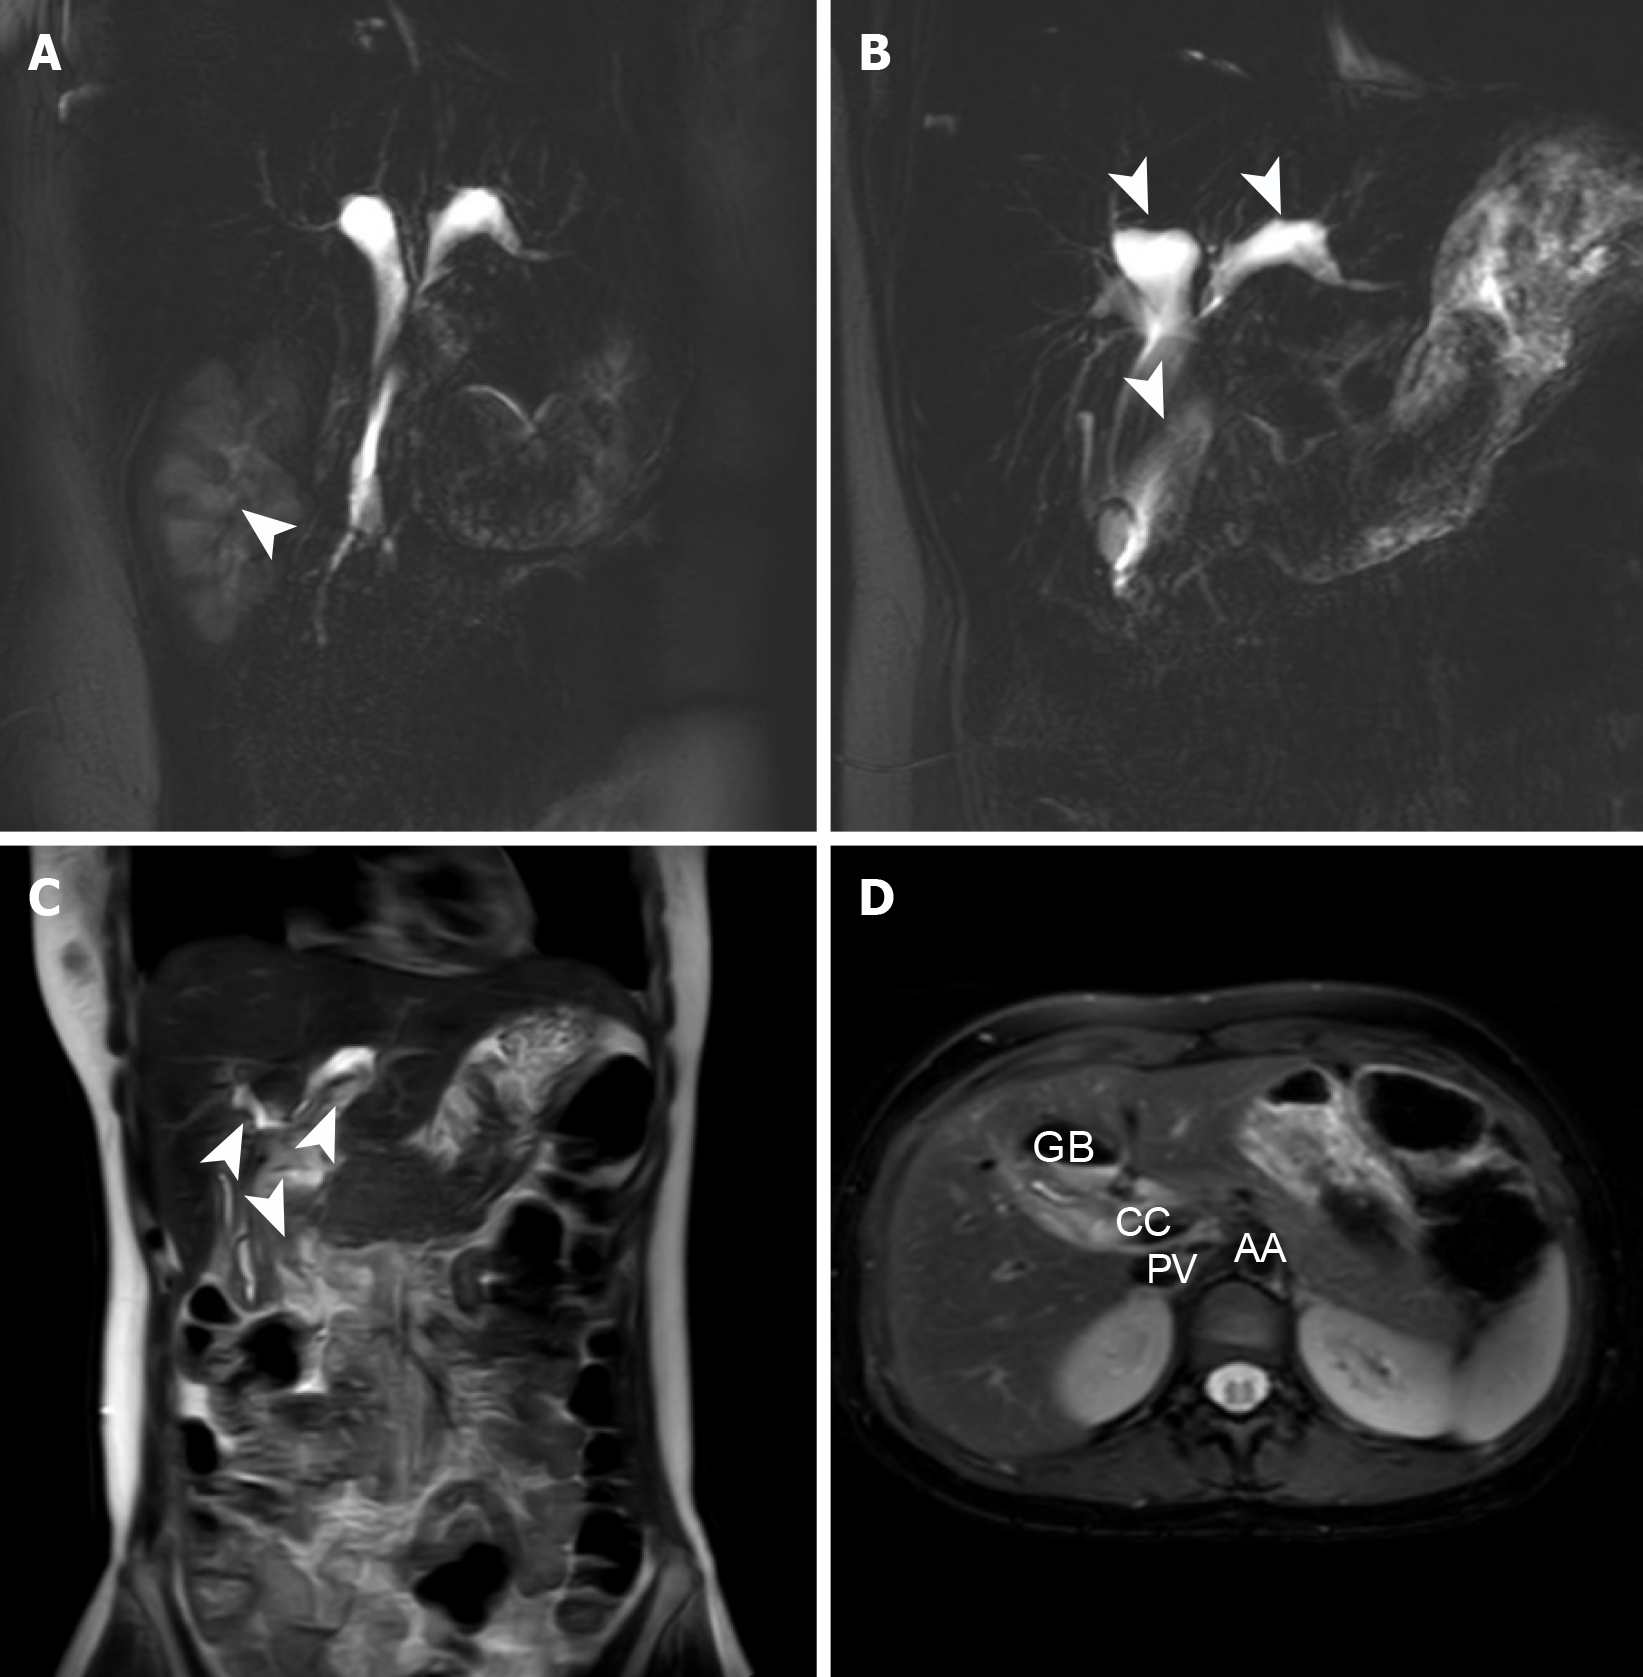

Six months later, the patient was readmitted for surgical treatment, and received a follow-up abdominal CT and MR abdominal scan + MRCP, which confirmed significant reduction in cyst expansion and hydronephrosis resolution (Figure 4). Laboratory parameters were within normal range (Table 3). Following a further clinical evaluation, the patient was deemed fit for surgery. Therefore, a comprehensive preoperative preparation was conducted, followed by cystectomy and Roux-en-Y hepaticojejunostomy through a laparoscopic approach. Postoperatively, the patient continued receiving antibiotics, fluid therapy, nutritional support, and treatment to maintain electrolyte and acid-base balance. On the first postoperative day, moderate ambulation was recommended to promote gastrointestinal function recovery. On the second day, the patient’s gastrointestinal tract became functional, and soft food was introduced. The patient did not report any discomforts. Postoperative pain was managed with opioid analgesics, which achieved good pain control. Details of the pathological findings on the surgical specimen are presented in the table below (Figure 5).